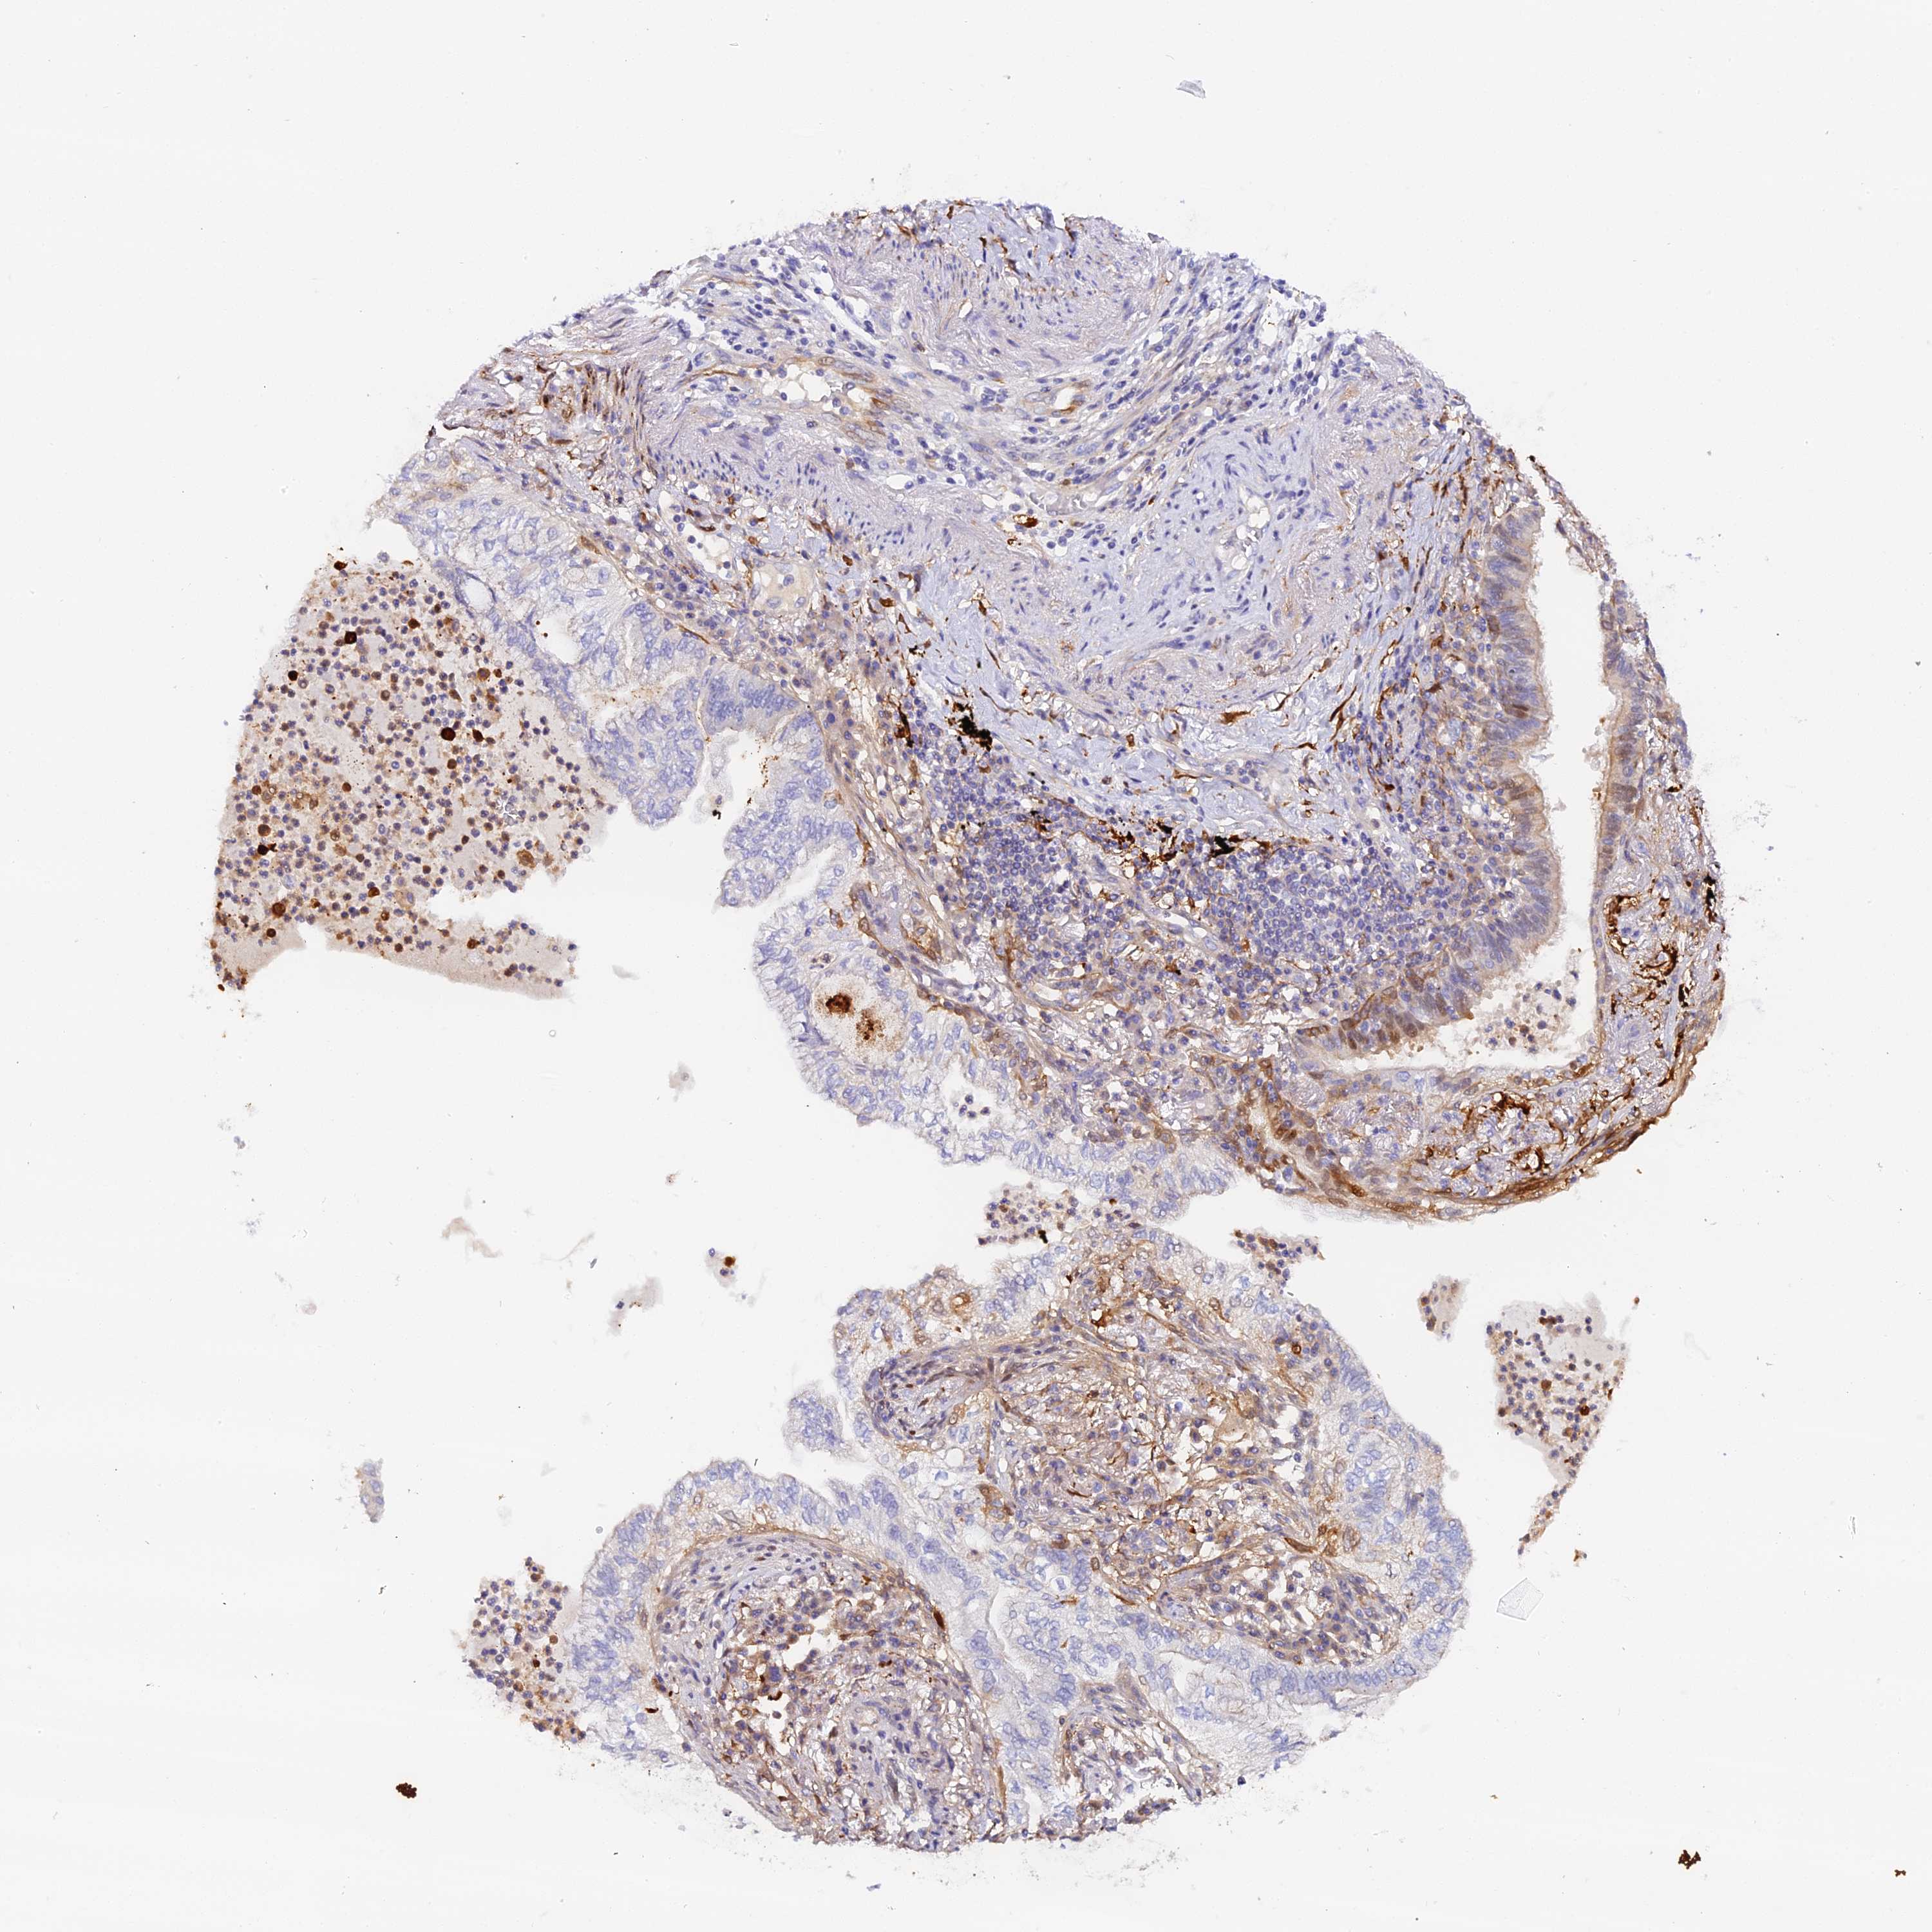

LUNG ADENOCARCINOMA (VALIDATION) - Interactive survival scatter ploti

The Survival Scatter plot shows the clinical status (i.e. dead or alive) for all individuals in the patient cohort, based on the same data that underlies the corresponding Kaplan-Meier plots. Patients that are alive at last time for follow-up are shown in blue and patients who have died during the study are shown in red.

The x-axis shows the expression levels (FPKM) of the investigated gene in the tumor tissue at the time of diagnosis. The y-axis shows the follow-up time after diagnosis (years). Both axes are complimented with kernel density curves demonstrating the data density over the axes. The top density plot shows the expression levels (FPKM) distribution among dead (red) and alive patients (blue). The right density plot shows the data density of the survived years of dead patients with high and low expression levels respectively, stratified using the cutoff indicated by the vertical dashed line through the Survival Scatter plot. This cutoff is automatically defined based on the FPKM cutoff that minimizes the p-score. The cutoff can be changed by dragging the vertical line or by entering a cutoff value in the square labeled "Current cut-off".

Under the Survival Scatter plot the p-score landscape (black curve; left axis) is shown together with dead median separation (red curve; right axis). Dead median separation is the difference in median mRNA expression between patients who have died with high and low expression, respectively. It is calculated as follows: median FPKM expression of dead patients with high expression - median FPKM expression of dead patients with low expression. This is intended to aid the user in visually exploring custom cutoffs and the associated p-scores and dead median separation.

Individual patient data is displayed and can be filtered by clicking on one or more of the category buttons on the top of the page. Categories describing expression level and patient information include: high, low, alive, dead, female, male and tumor stages. The scale of the x-axis can be toggled between linear and log-scale by clicking on the "x log" button. Mouse-over function shows TCGA ID, patient information and mRNA expression (FPKM) for each patient.

& Survival analysisi

Kaplan-Meier plots summarize results from analysis of correlation between mRNA expression level and patient survival. Patients were divided based on level of expression into one of the two groups "low" (under cut off) or "high" (over cut off). X-axis shows time for survival (years) and y-axis shows the probability of survival, where 1.0 corresponds to 100 percent.

KATNB1 is not prognostic in Lung Adenocarcinoma (validation)

: 5.65

Average pTPM 8.9

Number of samples 105